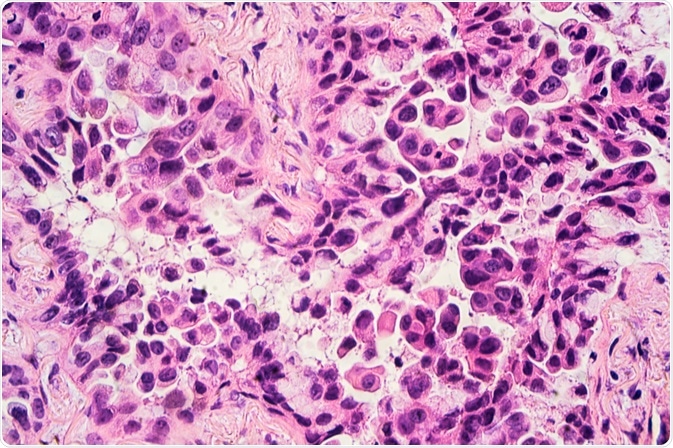

Image Credit: David A Litman/Shutterstock.com

Non-small cell lung cancer (NSCLC) can be further categorized into several different types, the most common of which include adenocarcinoma, squamous cell carcinoma (SCC), and large cell carcinoma. Other less common types of NSCLC include adenosquamous, pleomorphic, spindle cell, and giant cell carcinomas, as well as pulmonary blastoma, neuroendocrine tumors, and several others.

It is estimated that adenocarcinomas comprise approximately 40% of all lung cancers. By definition, adenocarcinoma in the lung is a malignant epithelial neoplasm that can be accompanied by either glandular differentiation or the production of mucin. Typically, an adenocarcinoma will form a peripherally located mass that exhibits both central fibrosis and pleural puckering.

Other gross appearances that can be associated with an adenocarcinoma diagnosis include a centrally located mass, diffuse lobar consolidation, multiple lobes distributed bilaterally, and pleural thickening.

Following a biopsy or tumor resection, an adenocarcinoma can be further characterized as a lepidic, acinar, papillar, micropapillary, solid, invasive mucinous, colloid, fetal, enteric, or minimally invasive carcinoma.